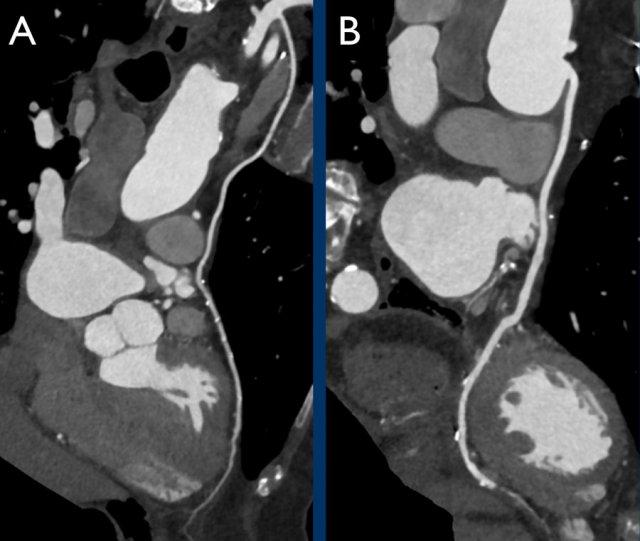

Example of a CTA scan performed on the same scanner in the same patient without (A) and with (B) administration of nitroglycerin, showing the increased diameter of the LAD. Due to the vasodilatory effect nitroglycerine increases the number of assessable (>1.5 mm diameter) segments.

Coronary CTA basics are:

- Administration of betablockers – if the heart rate > 65 BPM.

- Administration of nitroglycerine.

- Prospective ECG-gating or retrospectively gated helical mode.

- Calcium score reported in the form of Agatston score.

- Post-processing: axial image review, multiplanar reformation and maximum

intensity projection. - Optional image review: curved multiplanar reformation and volume

rendered reconstruction.